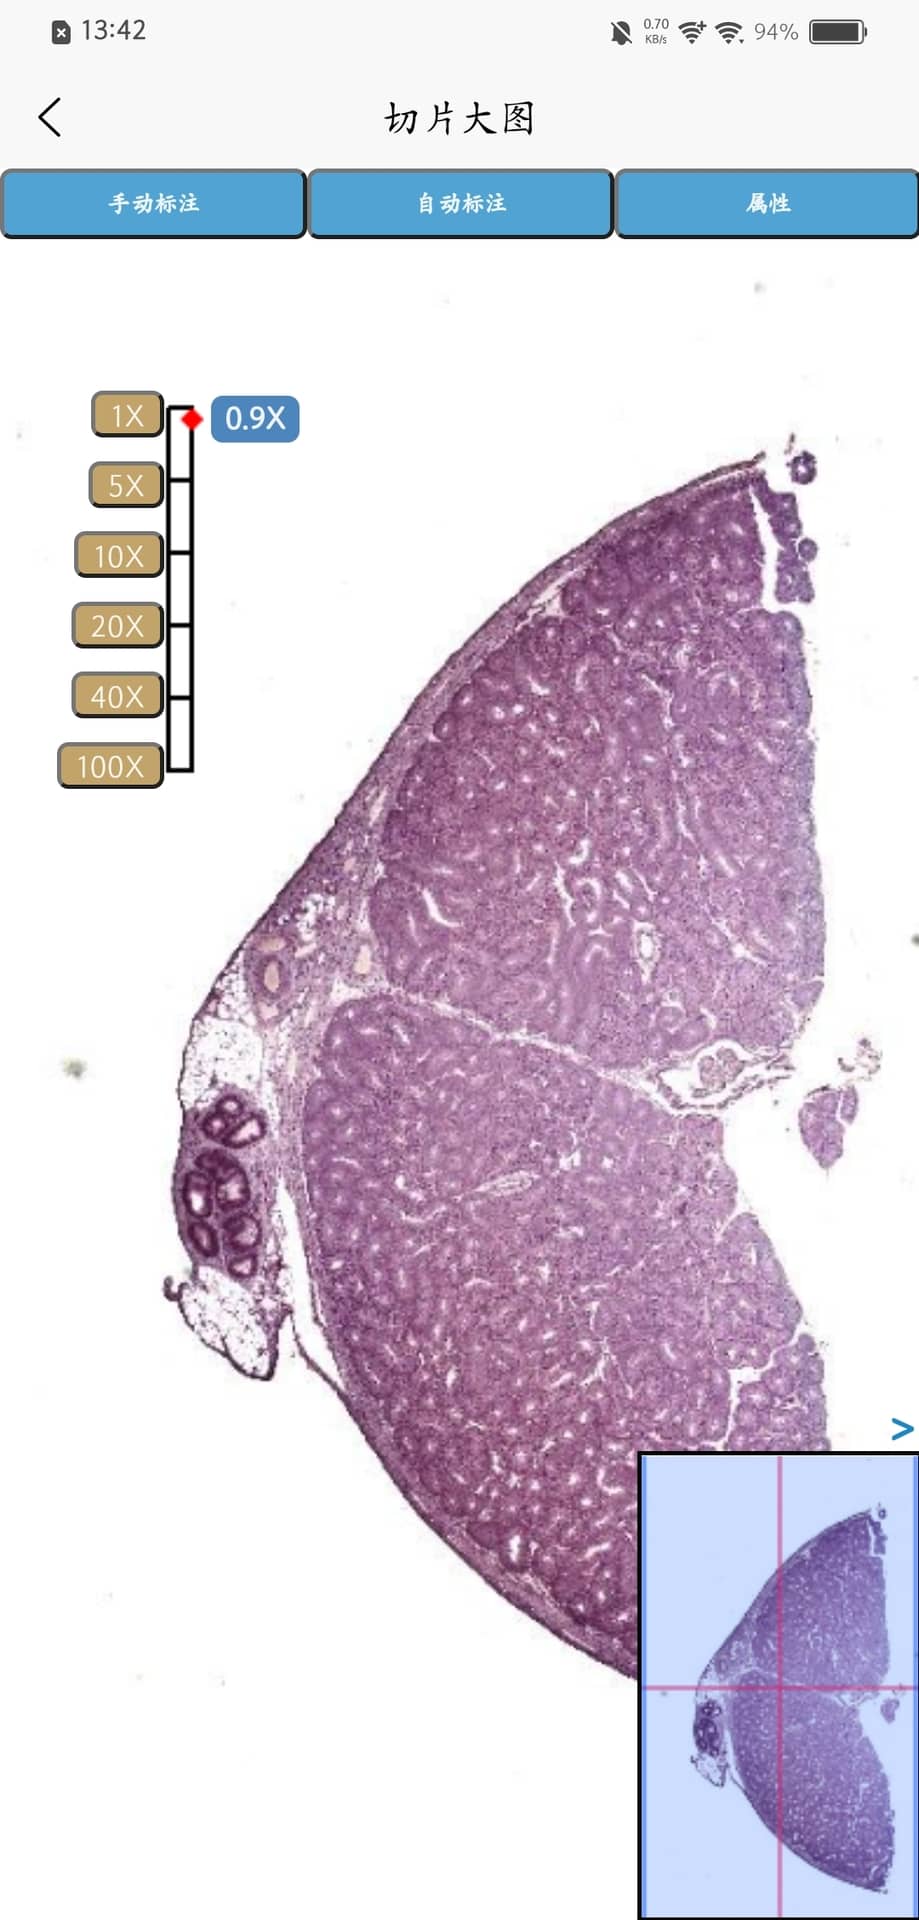

Turingene是一款由苏州迪美格智能科技有限公司开发的手机应用,专门用于病理切片的数字化扫描。用户只需使用手机即可对病理切片进行扫描,生成数字图像并方便地与他人共享。该应用能够帮助病理医生更快速、更高效地进行病情诊断,提升医疗效率和精准度。

Turingene是一款由苏州迪美格智能科技有限公司自主研发的App,用户可以通过此App,进行病理切片的扫描,扫描完成的切片可以进行内外部分享,协助病理医生病情诊断